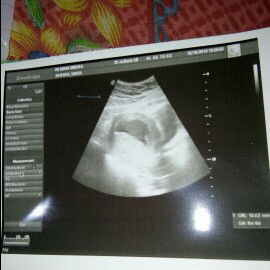

usg

Bun.. Aq hbs usg tdi kan itung an bidan 15 wek tp tdi di usg bru jaln 8wek. Terus kata dokter nya ko dedek ny gak aktif. Hrs ny di usia segitu udh aktif.. Trus 2mingg lgi suruh balik lgi.. Menurut bunda ada gak yg seperti aq .bagi pengalm nya bun

Bun semua minta doa nya aj ya.. Besok rencana mau usg du umur kehamiln 15wek.. Mogga diparingin lancar ..amiin